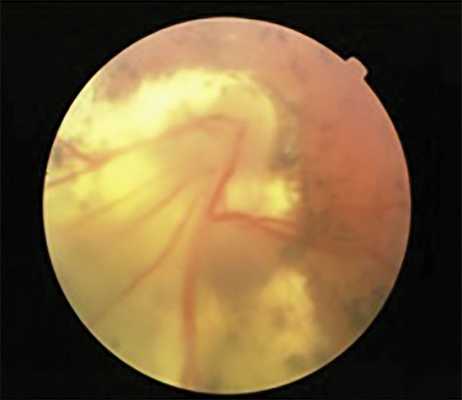

Развитие и прогрессирование ретинальных дистрофий привело к возникновению отслойки сетчатки на 13 глазах с II—IV степенью РН у детей в возрасте от 9 до 17 лет (в среднем в 14,1 года). При II степени РН отслойка сетчатки носила регматогенный характер (5 глаз), а при III и IV степени — регматогенный и тракционно-регматогенный характер (8 глаз), что потребовало комбинированных хирургических вмешательств (рис. 5).

Рис. 5. Поздняя субтотальная отслойка сетчатки регматогенного характера на глазу с РН II степени и частичной атрофией зрительного нерва.

Поздняя отслойка сетчатки диагностирована на 62 глазах через 1,5-16 лет после активно фазы РН. Пик развития отслойки сетчатки приходится на 11-14 лет (82%). В отличие от первичных экссудативно-тракционных отслоек сетчатки, развивающихся при прогрессировании активной РН, отслойки сетчатки в рубцовой фазе заболевания носят регматогенный или тракционно-регматогенный характер и являются следствием развития или прогрессирования витреоретинальных осложнений (рис. 2).

На 25 из 29 глаз (86%) с РН 0-II степенью развитию отслойке сетчатки предшествовало прогрессирование периферических дистрофий сетчатки с образованием одиночных или множественных истончений и разрывов сетчатки. При III степени РН причинами развития поздней отслойки сетчатки в большинстве случаев (30 из 32 глаз) было прогрессирование пре- и интраретинального фиброза, приведшее к усилению тракции сетчатки в центральных и периферических отделах, развитию тракционной или тракционно-регматогенной отслойки сетчатки (рис. 3). В двух случаях отслойка сетчатки была спровоцирована травмой.